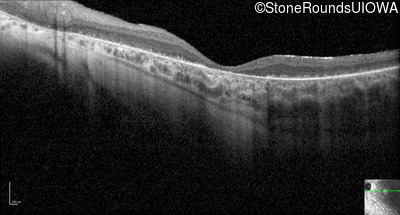

Optical Coherence Tomography - Right - 5/225

Exemplar / OCT Stack

OCT Stack